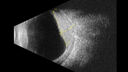

Choroidal hemangioma 10 year old black male11 views10 year old black child The patient has been wearing glasses which for 3 years and the left eye has had a changing prescription.

3/13/23: OD: +1.00; OS: +5.50

7/18/24: OD: +1.00; OS: +8.00 -1.25 x 015

2/3/25: (Cycloplegic): OD: +2.00; OS: 11.50+1.50 x 120

She had an MRI scan was not diagnostic.

VA OD:20/16

OS: 20/30-2

B-scan 5.1 mm H x 12.3 mm A x 15.0 mm T highly reflective mass centered just temporal to the macula involving the entire macula).

Seen at Wills and observation was decided because of no macular fluidAug 13, 2025